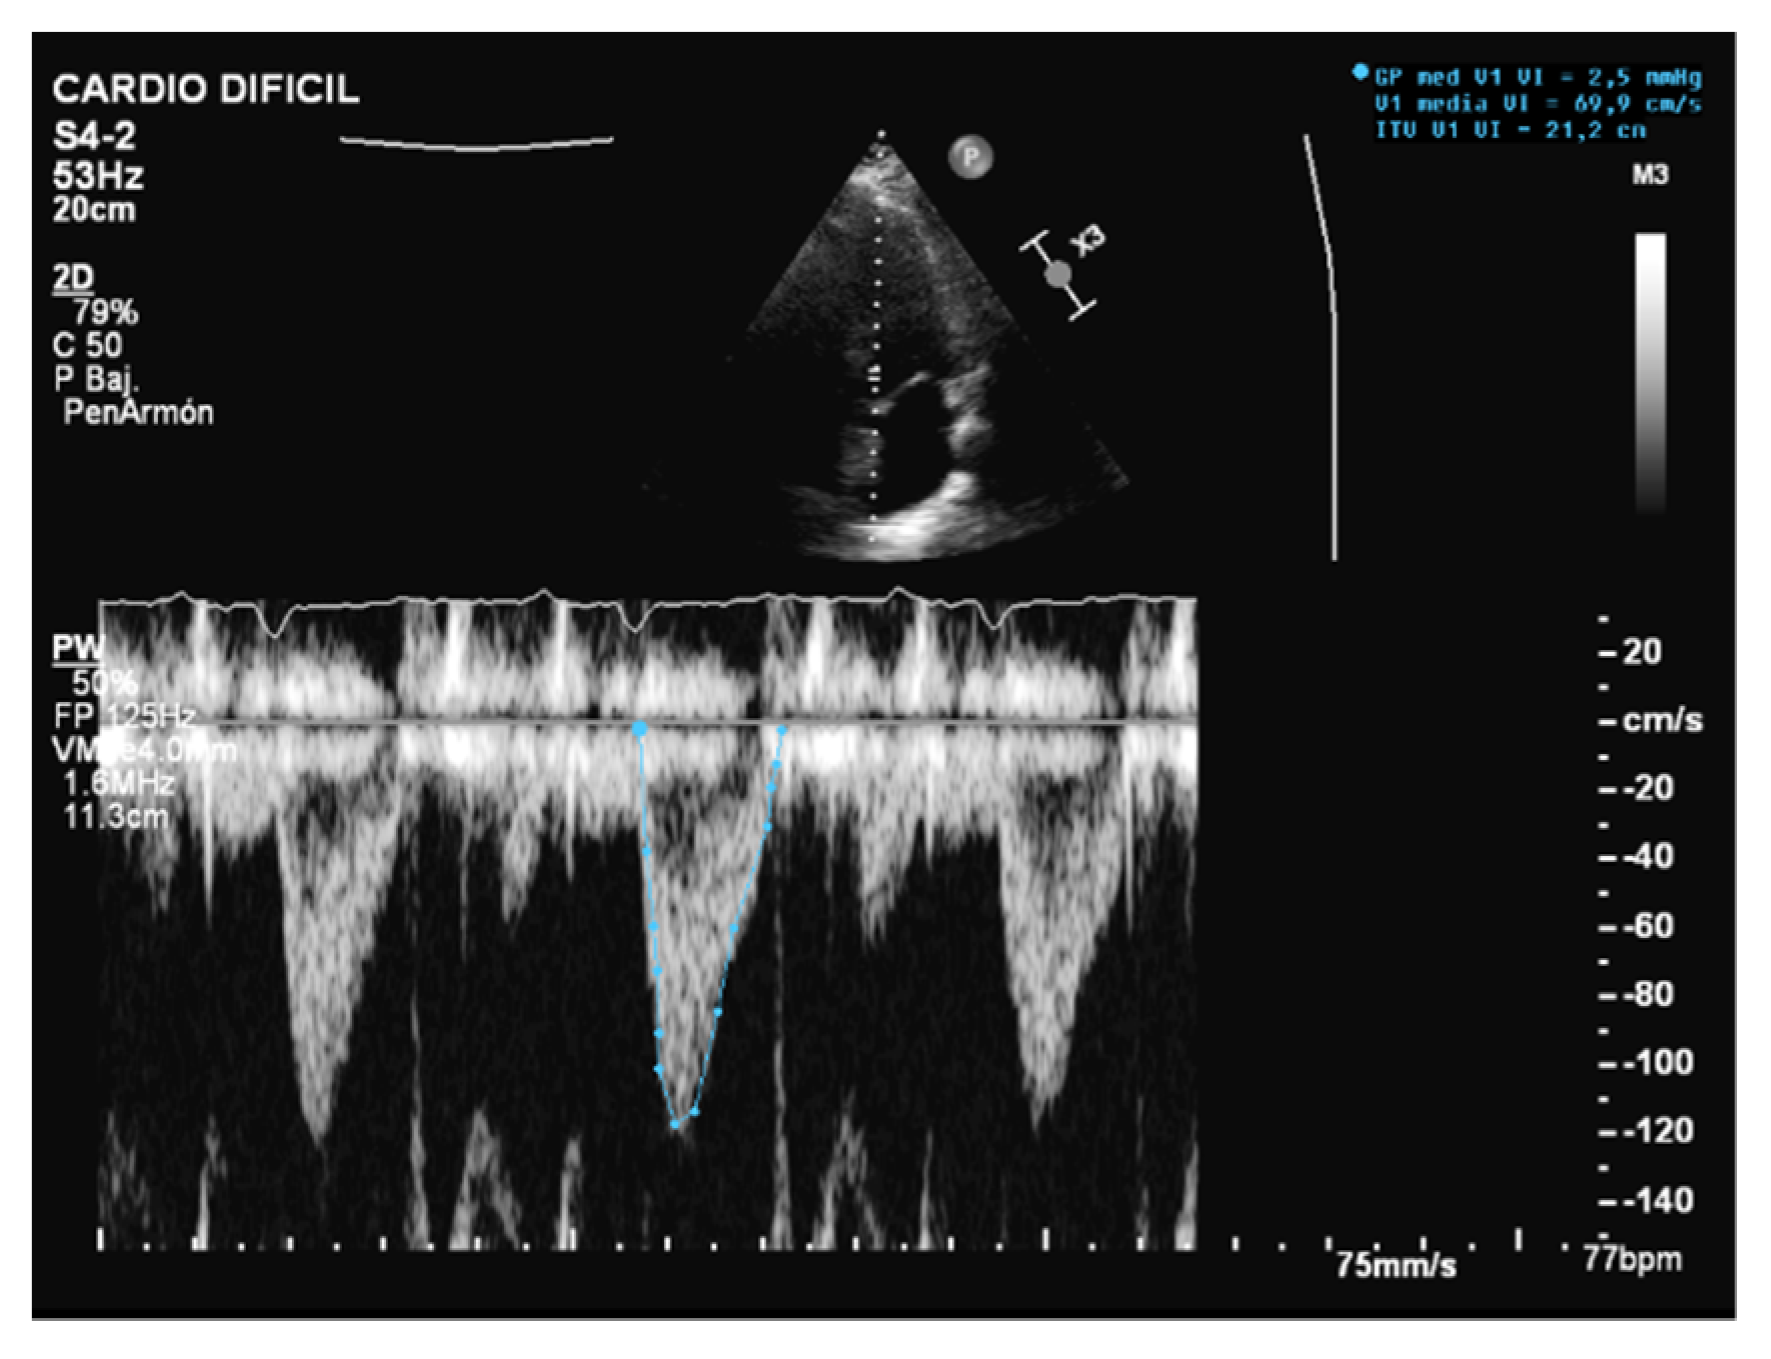

Unlike MV weaning assessment, evaluation of systolic function is the key factor in the decision to wean from ECMO. Weaning can be attempted when the ejection fraction of the left ventricle is higher than 35% and/or the left-ventricular outflow tract velocity time integral (VTI) is higher than 15 cm/s, with a minimal ECMO flow under 1.5 L/min or less than 1500 rpm [9]. Previous studies have also proposed lower values of both ejection fraction (around 20–25%) and VTI (10 cm/s) for a successful weaning [32,33] (Figure 3 and Figure 4).

Figure 3.

Normal left-ventricular outflow tract velocity integral (VTI).